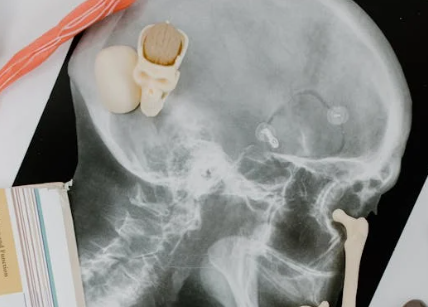

이로 인해 다양한 신경학적 모야모야병 증상이 나타나며, 혈관조영술에서 연기처럼 피어오르는 가느다란 혈관 모양이 보여 ‘모야모야(もやもや)’라는 이름이 붙게 되었어요.

MRI & MRA로 뇌혈관 상태를 전체적으로 파악하고, 뇌혈관 조영술로 ‘연기처럼 피어나는 혈관’ 모양을 확인하며 SPECT 검사를 통해 뇌혈류 흐름을 측정해 수술 여부를 결정하게 됩니다.